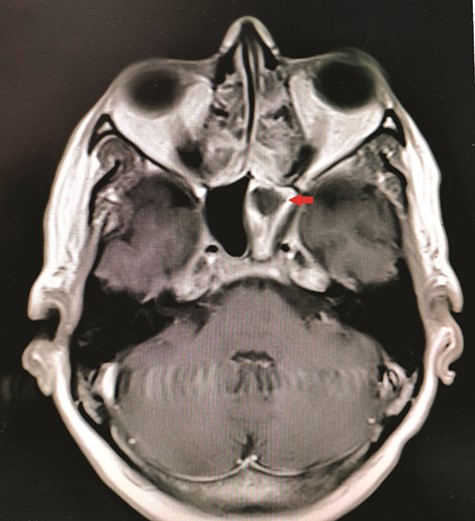

CT unveiled calcified densities within areas of hypoattenuation in the left sphenoid sinus. No marked bony destruction was observed (Fig. 2). A subsequent magnetic resonance imaging (MRI) was carried out to show hypodensity on T1 weighted post-contrast, and flow void in T2 weighted images within the same sinus (Figs. 3 and 4). Following informed consent, an emergency endoscopic left trans-ethmoidal sphenoidotomy was performed under general anaesthesia. A dense, darkened clay-like mass surrounded with the mucopurulent discharge was noticed within the left sphenoid sinus. The mucosa appeared inflamed and oedematous without clinical evidence of frank necrosis. The debris was utterly removed with a curette and sent for evaluation. The left sphenoid sinus was widened and thoroughly rinsed.

Axial view of MRI T1 weighted post-contrast showed hypodensity within the left sphenoid sinus with surrounding inflammation (red arrow).